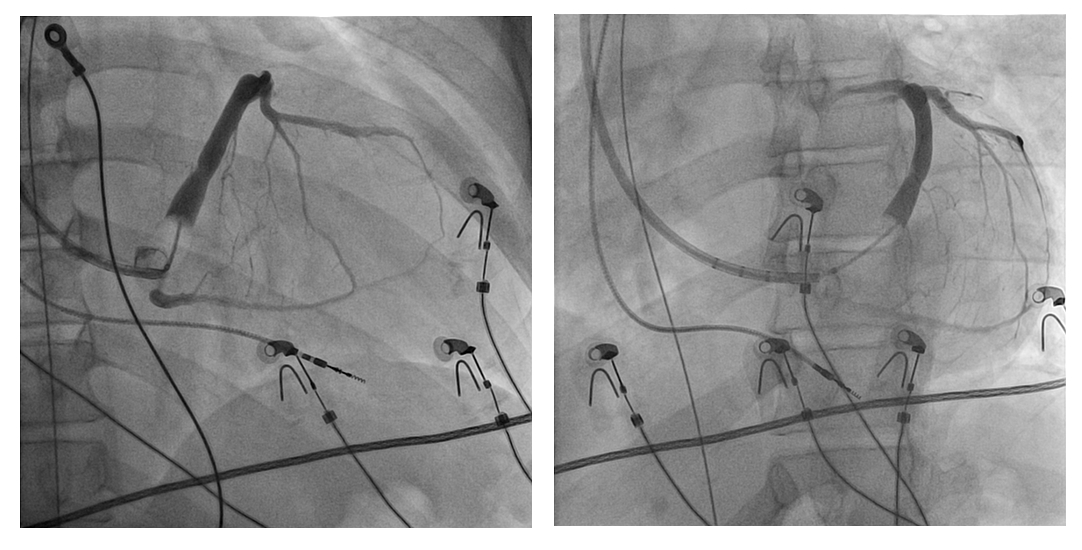

CS venogram

venogram_lao_rao.jpg

CS lead through subselective catheter

lead_subselective.jpg

Left bundle lead in place

LB_lead.jpg

Final position

final_position.jpg

Final ECG

as_biv_pace.jpg